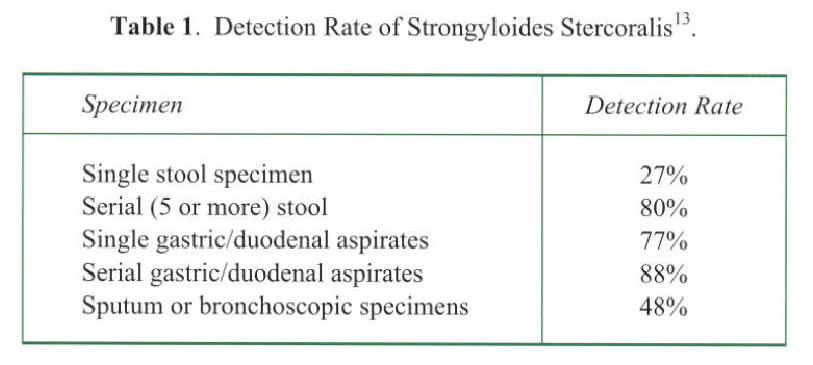

Radiological features are also diverse and variable 15,16.On the chest radiograph, early signs include miliary shadows, diffuse reticular interstitial opacities, patchy alveolar opacities, segmental or lobar opacities. In the advanced stage, there can be extensive airspace shadows affecting both lungs, with occasional pleural or pericardial effusion. Without treatment, ARDS quickly evolves. Rarely, ARDS develops after antihelminthic treatment due to release of toxic breakdown products 17.On the abdominal radiograph, there can be thickened mucosal folds, segmental small bowel dilatation or perforation. Among all these variable radiological features, a characteristic pattern of Strongyloides hyperinfection has been described by the radiologists of Hong Kong, which consist of fleeting and rapidly changing CXR signs, predominant small bowel abnormality on AXR, and close temporal relationship of CXR & AXR signsl8. Detection of larvae in stool or other specimens is difficult (Table 1). Serological diagnosis19 is an attractive alternative but it is not available in Hong Kong.

Radiological features are also diverse and variable 15,16.On the chest radiograph, early signs include miliary shadows, diffuse reticular interstitial opacities, patchy alveolar opacities, segmental or lobar opacities. In the advanced stage, there can be extensive airspace shadows affecting both lungs, with occasional pleural or pericardial effusion. Without treatment, ARDS quickly evolves. Rarely, ARDS develops after antihelminthic treatment due to release of toxic breakdown products 17.On the abdominal radiograph, there can be thickened mucosal folds, segmental small bowel dilatation or perforation. Among all these variable radiological features, a characteristic pattern of Strongyloides hyperinfection has been described by the radiologists of Hong Kong, which consist of fleeting and rapidly changing CXR signs, predominant small bowel abnormality on AXR, and close temporal relationship of CXR & AXR signsl8. Detection of larvae in stool or other specimens is difficult (Table 1). Serological diagnosis19 is an attractive alternative but it is not available in Hong Kong.